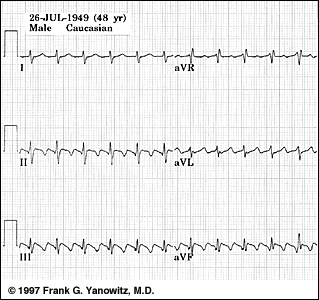

TULBURARI DE RITM SI DE CONDUCERE

TULBURARI DE RITM SI DE CONDUCERE 1. Flutterul atrial Este o disritmie produsa prin depolarizari atriale regulate, rapide, cu o frecventa de 250-350/min Apare un BAV care face ca numai o parte din impulsurile atrialeCiteste tot ... 518 cuvinte

Dimensiune mica

+ cu imagini |